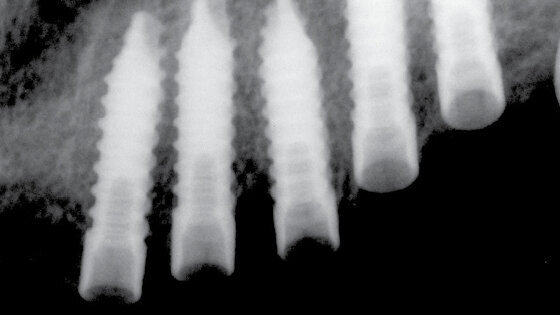

UIS IMPLADENTA obsahuje kompletní nabídku jednofázových a dvoufázových implantátů. Mini samořezné (MS), bikortikální samořezné (BS) – jednofázové implantáty. V nabídce současně dvoufázové úzké válcové (NS) a cylindrické samořezné implantáty (CS) včetně abutmentů. Celistvost a kompletnost zajištuje speciální nabídka čepelkových – plátkových implantátů řada PROFI+.

Implantáty UIS IMPLADENTA jsou vyráběny z certifikovaného biokompatibilního materiálu 99,6% Titanu Gr.4. Na dentální trh se dodávají v praxi vyzkoušených požadovaných rozměrech včetně individuálních rozměrů mimo standardní nabídku na vyžádání.

ŘADA PROFI+ je určena pro zkušené implantology. Z poznatků uživatelů je patrné, že plátkové – lístkové jednofázové implantáty B1 a B2 jsou považovány za 100% spolehlivé.

Sériová výroba nejčastěji používaných plátkových implantátů nabízí více než 50 druhů tvarů implantátů a umožňuje jejich velmi široké klinické využití.

Implantát řady PROFI+ má 6mm matné, zdrsněné části, následuje 5mm lesklý povrch s bodem pro určení, kam musí zasahovat implantát do kostní tkáně. Nitrokostní část je matná a zdrsněna pískováním s otvory pro zvýšení sekundární stability.